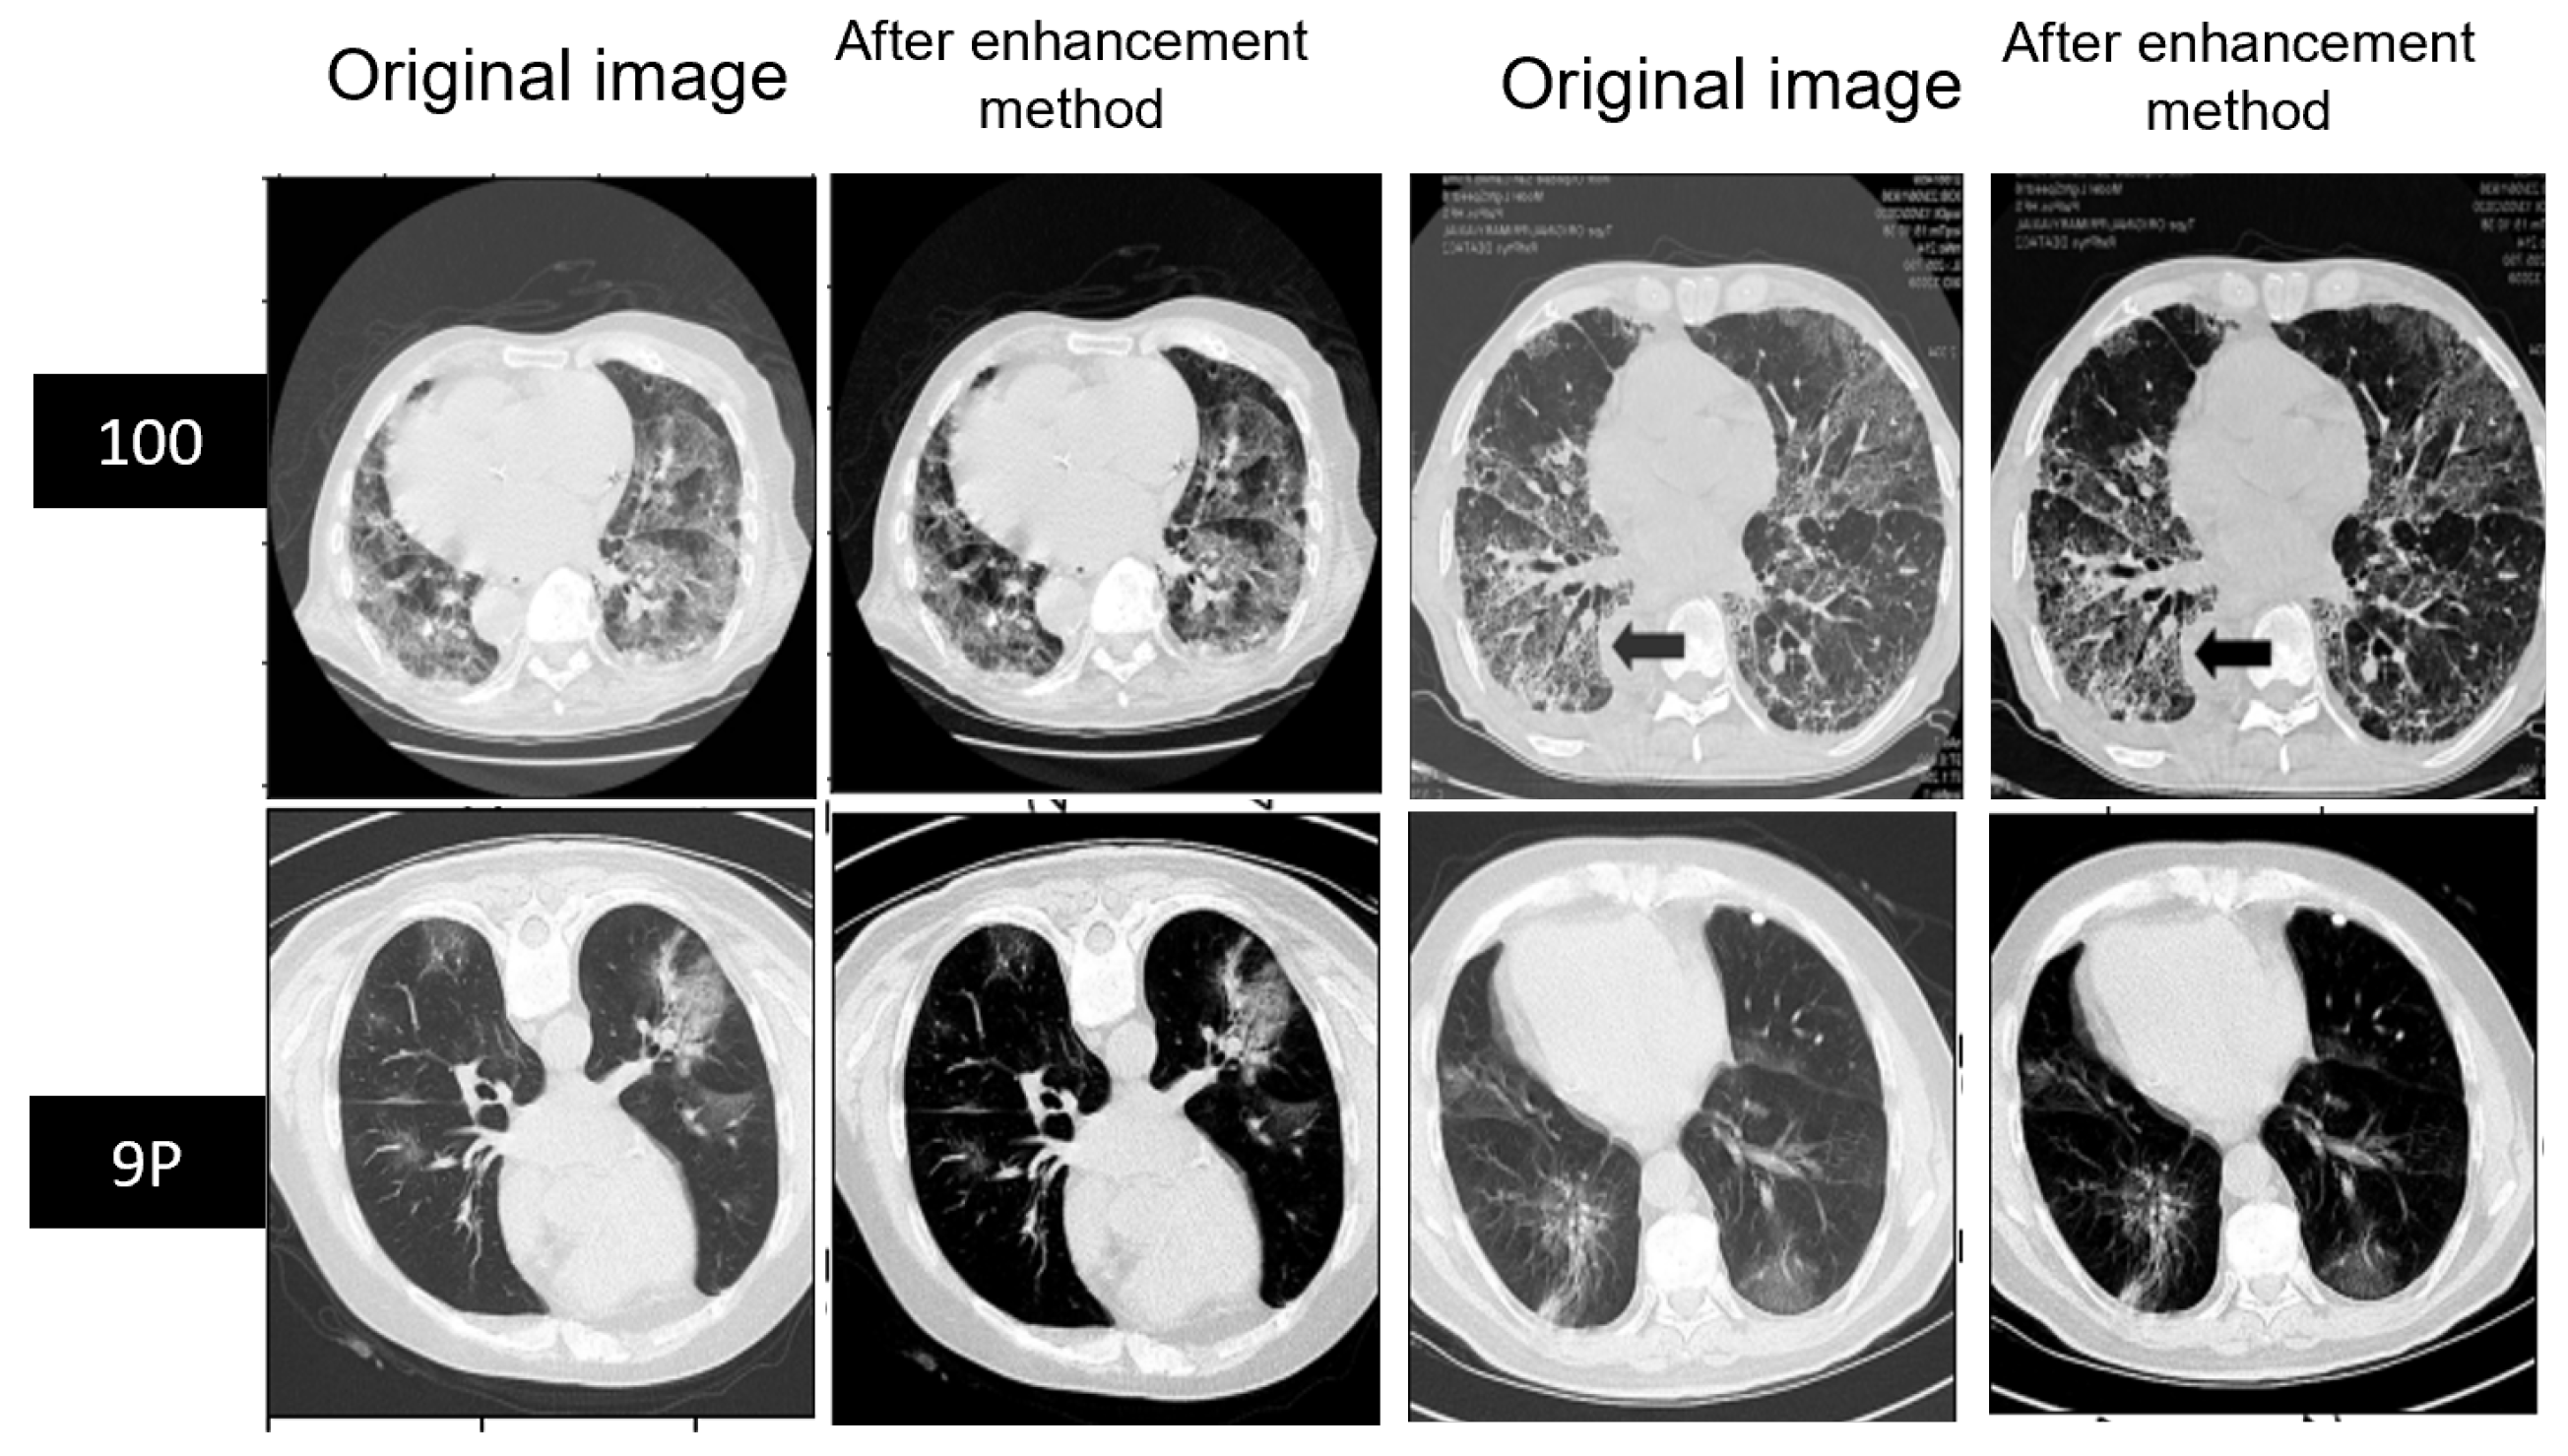

Figure 7.

Example of MedSeg and Radiopaedia before and after enhancing the contrast of slices.

In CT imaging, contrast enhancement methods can be applied for infection segmentation to improve the visibility of the areas affected by the infection. This can highlight the areas of interest and make them more distinguishable from the background. However, ensuring that the contrast enhancement does not introduce artifacts or noise that may negatively impact the segmentation accuracy is also important.

The contrast enhancement method was influential in training unclear CT scan images. As shown in Table 5, this method affected the segmentation of the infection and background classes and improved the segmentation process. The MedSeg dataset was improved by 2.4%, whereas Radiopaedia 9P was improved by 1.3% with respect to the mean Dice score compared to without the enhanced contrast method. Furthermore, the mean IOU of MedSeg was improved by 2.2%, whereas the Radiopaedia 9P was the same. This contrast enhancement method of the poor contrast in the MedSeg dataset significantly improved all the evaluation metrics. In addition, the Radiopaedia 9P dataset was improved in the sensitivity and the mean Dice score, especially the Dice score for infection, positively affecting recognizing the foreground and distinguishing it from the background by 1.3%. Figure 12 shows an example of a predicted slice of the same slice fold trained with and without the contrast enhancement method. It is easy to notice that the improvement happened after enhancing the contrast of the MedSeg dataset, whereas for Radiopaedia-9P, the mask was predicted almost as well as without contrast enhancement with no adverse effect on it. As a generalization of the training model, we tested each SAA-UNet trained on one dataset and tested on different datasets. The results are shown in Table 6. The performance metrics decreased while testing on other datasets compared to testing on the same dataset. First, the model trained on Radiopaedia had good results while testing on the MedSeg dataset than on the Zenodo 20P dataset. The SAA-UNet model trained on the Zenodo 20P dataset had the best generalization when tested on the other datasets after applying the contrast enhancement method to ensure the effectiveness of this method. The number of CT slices on which the model was trained and the apparent contrast of the original images led to this generalization and gave promising results. The model trained on the MedSeg dataset showed better results when tested on Radiopaedia 9P than the Zenodo 20P dataset. In contrast, the models trained on the MedSeg + Radiopaedia 9P dataset and then tested on the Zenodo 20P dataset were better than those trained on MedSeg. SAA-UNet had a good generalization for the different training dataset experiments.

Figure 12.

The effect of the contrast enhancement method on predicted images of each fold. The blue in the first two rows is for the MedSeg dataset, and the brown is for the Radiopaedia 9P datasets.